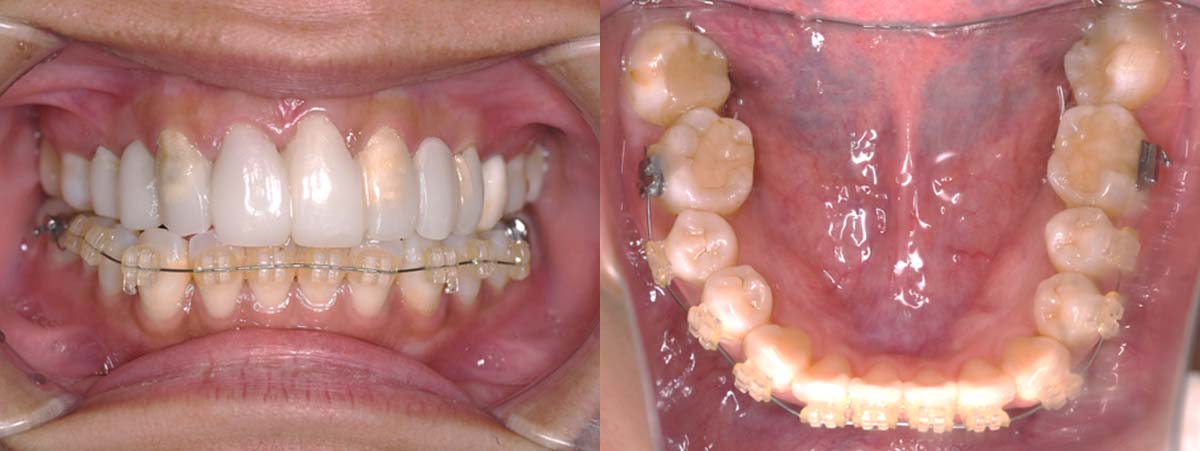

スプリント使用後、

補綴治療をした症例

2024年 10月 下顎MTM開始